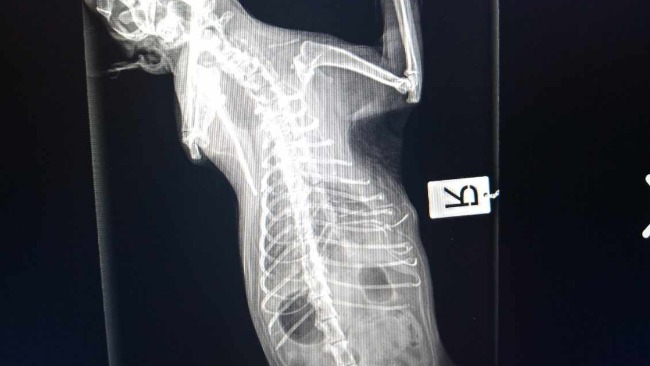

Wczoraj miał słabszy apetyt a dzisiaj rano drastycznie zaczęła mu spadać temperatura, poniżej 36 stopni. Natychmiast pojechał do lecznicy gdzie został poddany wstępnej diagnostyce, jednak ponieważ zaczął się u niego zbierać płyn w klatce piersiowej nieznanego pochodzenia i wystąpiła silna duszność musiałam go przewieźć na sygnale do lecznicy całodobowej. Tam trwa dalsza diagnostyka, zostało wykonane rtg, usg, zbadana krew ale nadal nie mamy przyczyny jego ciężkiego stanu.